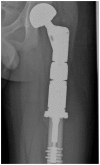

Less than 10% of chondrosarcomas occur in children. In addition, as little as 0.5% of low-grade chondrosarcomas arise secondarily from benign chondroid lesions. The presence of focal pain is often used to crudely distinguish a chondrosarcoma (which is usually managed with wide surgical excision), from a benign chondroid lesion (which can be followed by clinical exams and imaging surveillance). Given the difficulty of localizing pain in the pediatric population, initial radiology findings and short-interval follow-up, both imaging and clinical, are critical to accurately differentiate a chondrosarcoma from a benign chondroid lesion. To our knowledge, no case in the literature discusses a chondrosarcoma possibly arising secondarily from an enchondroma in a pediatric patient. We present a clinicopathologic and radiology review of conventional chondrosarcomas. We also attempt to further the understanding of how to manage a chondroid lesion in the pediatric patient with only vague or bilateral complaints of pain.